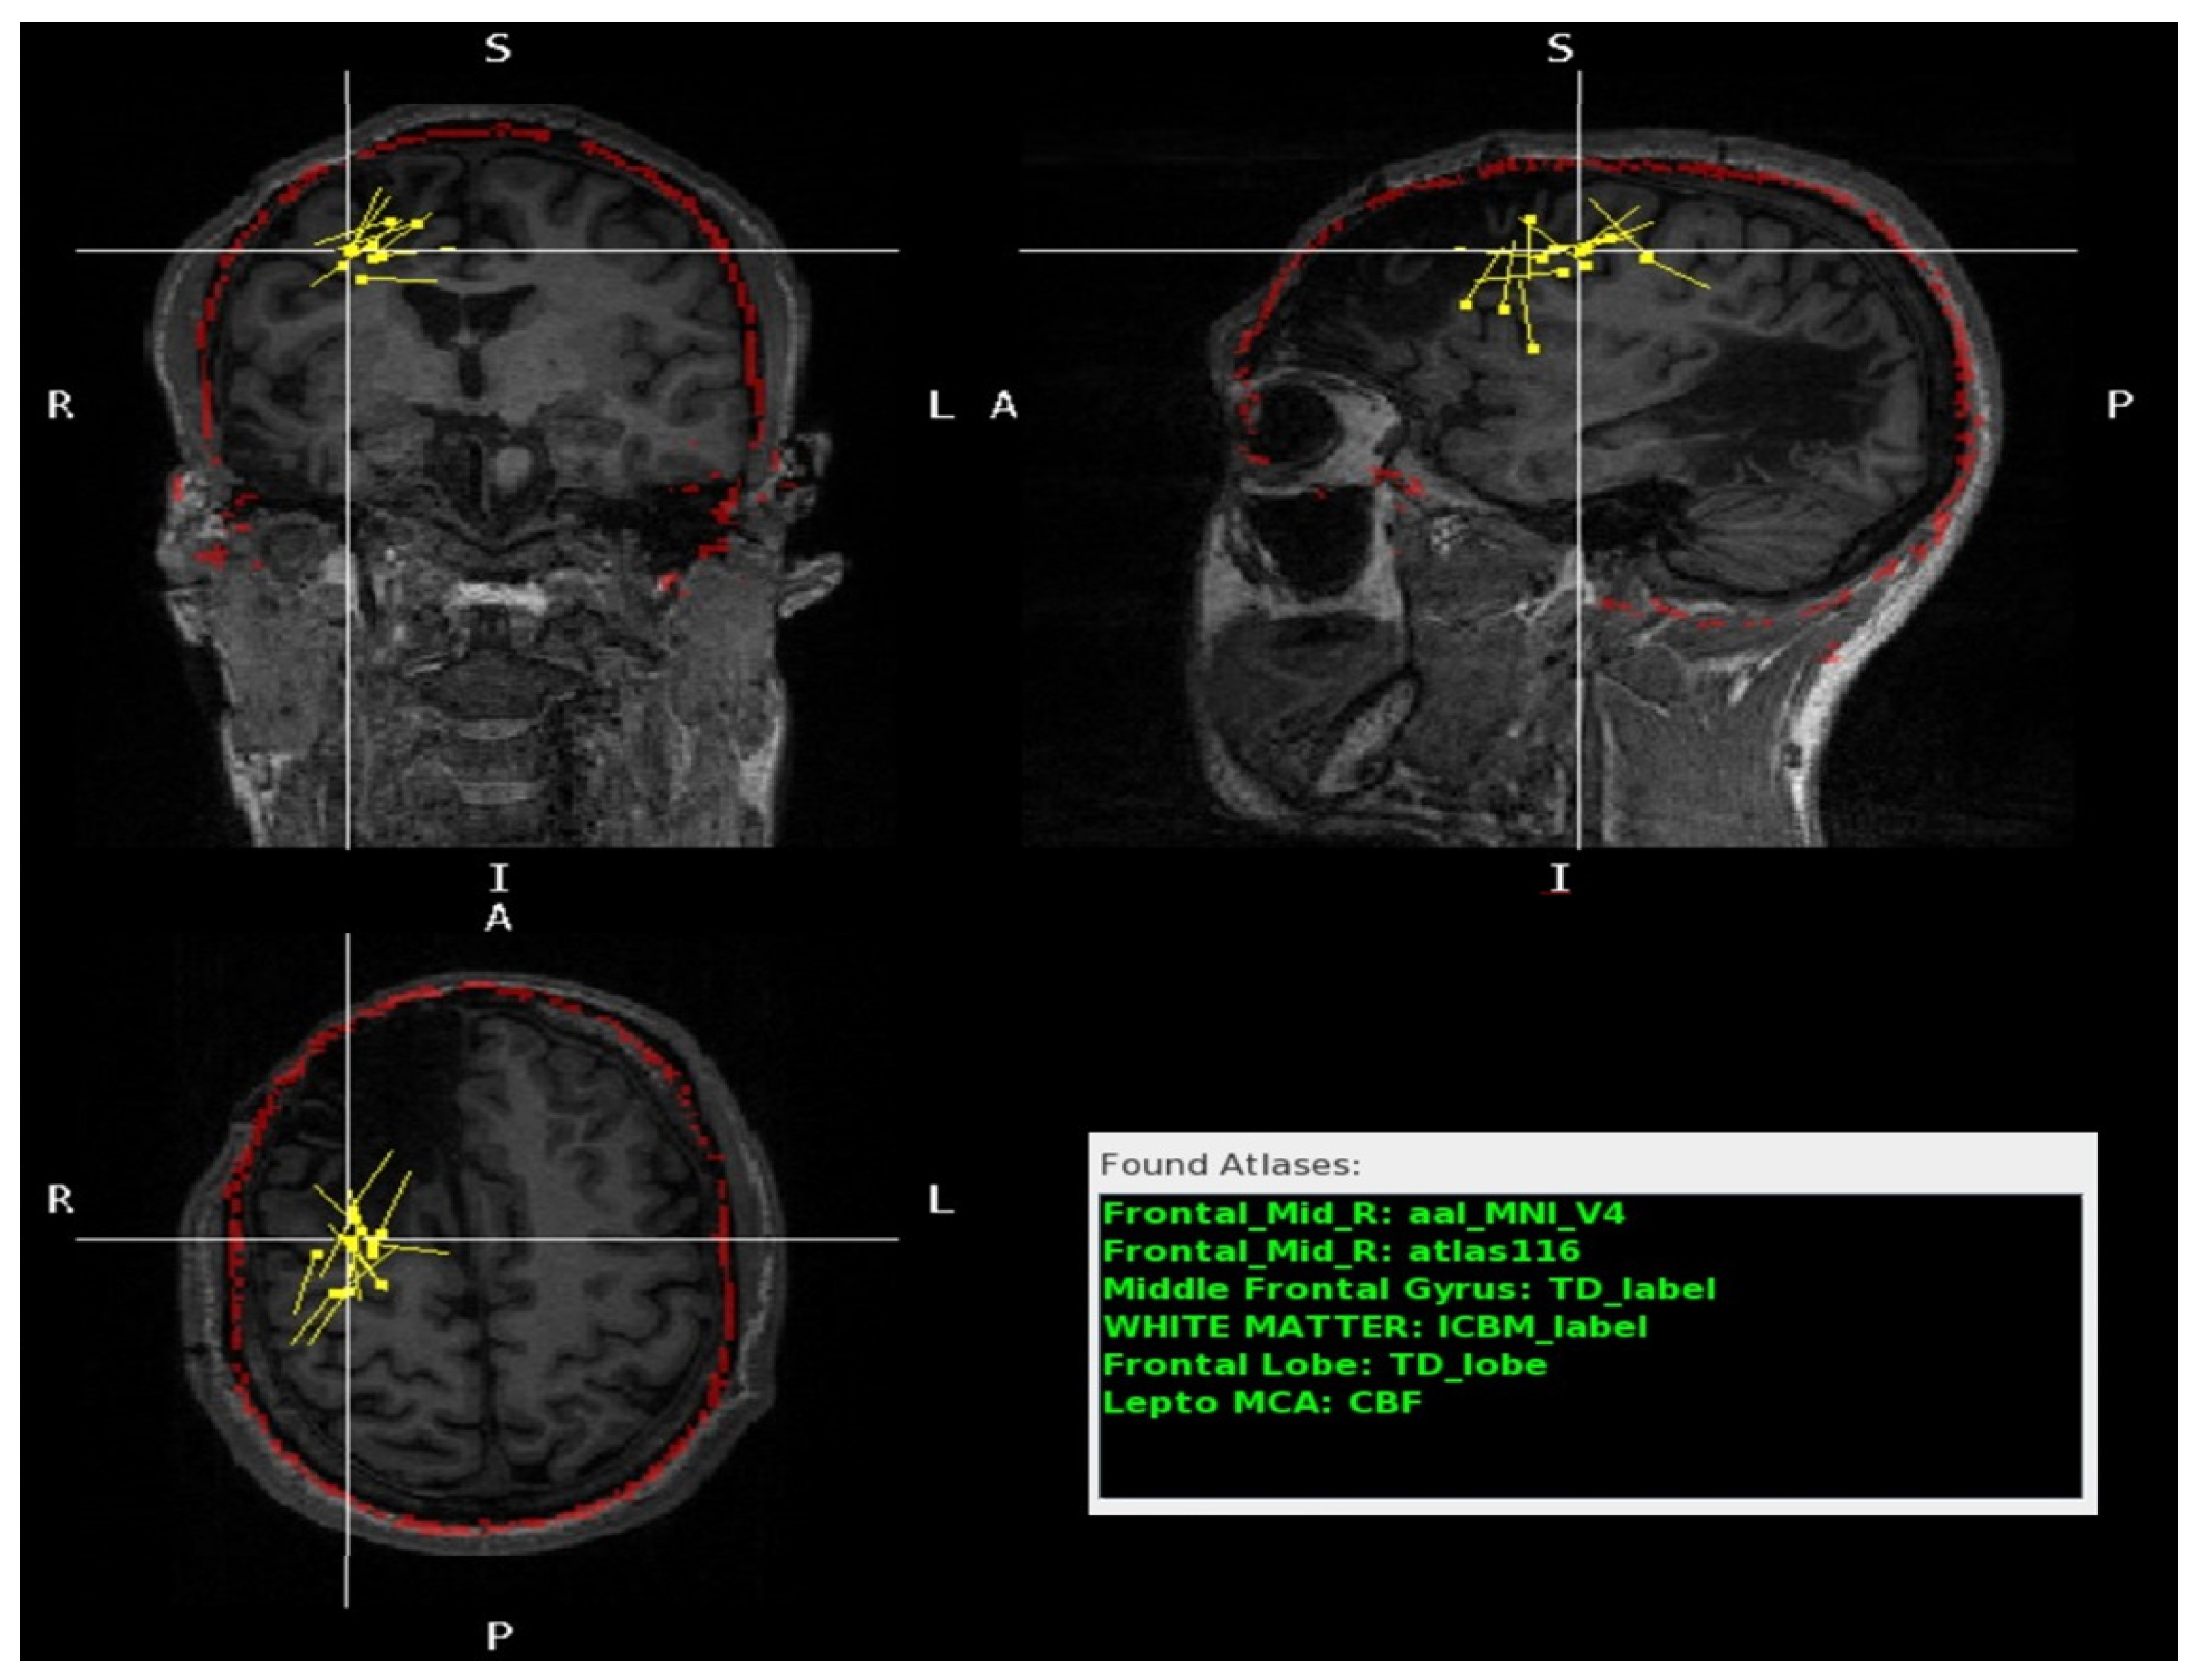

3.1. Usage of the Program Tools